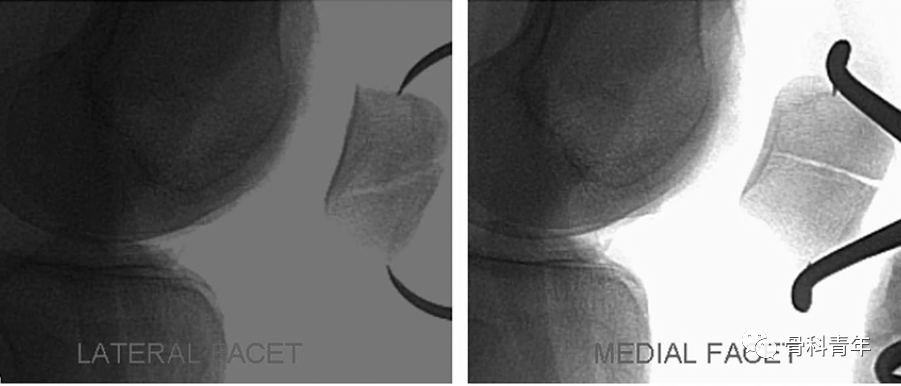

影像上,髌骨内外侧关节面均为倾斜面,在正常侧位上无法有效评估。

在常规膝关节侧位上,髌骨内外侧关节面重叠,显示不清

有学者研究表明,在髌骨外旋24°可在侧位上评估外侧关节面复位情况,内旋34°可以评估内侧关节面情况。

通过膝关节外旋,可以观测外侧关节面,膝关节内旋后可以观测内侧关节面